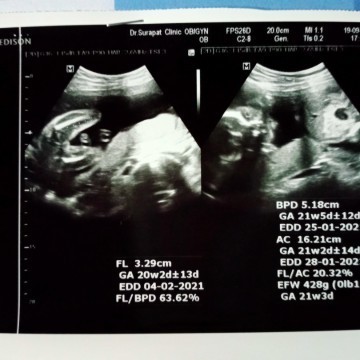

มาอวดรูปตอนซาวด์กันหน่อยค่ะ แม่ๆกำหนดคลอดเดือนไหนบ้างคะ